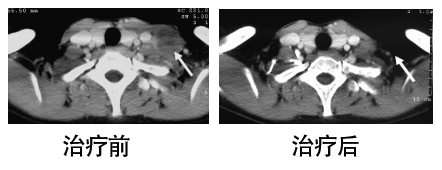

ACTL科研治疗一个月后,即二次治疗后,患者病情好转,胸部疼痛明显减轻。CT复查显示:胸腔积液较前减少。两肺多发微小结节,较前片明显缩小、减少。

ACTL科研治疗前后对比:

治疗前影像学示:两肺多发小结节,考虑转移性肿瘤。纵膈内多发轻度肿大淋巴结。

治疗后影像学示:两侧多发微小结节,较前片明显缩小、减少。